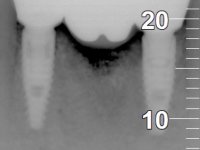

Paciente do sexo feminino com 62 anos, fumadora. 10 Anos atrás tinha sido colocado um implante na zona dos dentes 41 e 42 para reabilitar com uma ponte de dois elementos a falta destes dois dentes. Feito o exame imagiologico foi observada uma perda óssea junto ao implante compatível com uma peri-implantite. A parede óssea vestibular junto ao implante apresentava uma extensa reabsorção, estando a superfície vestibular do implante em contacto com os tecidos moles e numa determinada zona um orifício permitia a visualização do implante através do tecido gengival. Os dentes 42 e 32 apresentavam já alguma mobilidade.

Após estudo imagiológico foi planificada a colocação de dois implantes de 3.3 mm de diâmetro e 10 mm de comprimento. No dia da cirurgia foram extraídos os dentes 42 e 32 e removido o implante. Os implantes foram colocados na zona dos alvéolos tendo o cuidado de lingualizar um pouco o seu posicionamento. Foi feita uma impressão pela técnica de moldeira aberta com o retalho aberto para a confeção da ponte provisória imediata. Enquanto a impressão foi para o laboratório, foram colocados parafusos de cicatrização altos e feita a sutura da ferida cirúrgica. A paciente esperou 2 horas na sala de espera enquanto no laboratório era confecionada a ponte provisória. A ponte provisória imediata aparafusada foi colocada e o seu assentamento controlado imagiologicmente. Passados 3 meses foi realizada a impressão definitiva com uma técnica de moldeira aberta. Nessa consulta aproveitamos para polir a ponte provisória com taças de borracha para que os tecidos moles pudessem maturar em melhores condições. Foi feita a recolha de informação para caracterizar da melhor forma a estrutura monolítica em Zr. Foram utilizadas guias de cor para a cerâmica de tonalidade coronária e gengival. No laboratório foi confecionada uma ponte em Zr. aparafusada que foi cuidadosamente caracterizada. Após aprovação pela paciente foi colocada definitivamente em boca. O aperto foi feito com uma chave dinâmica com 35 N de torque. Os orifícios foram tapados com teflon e obturados com resina composta.